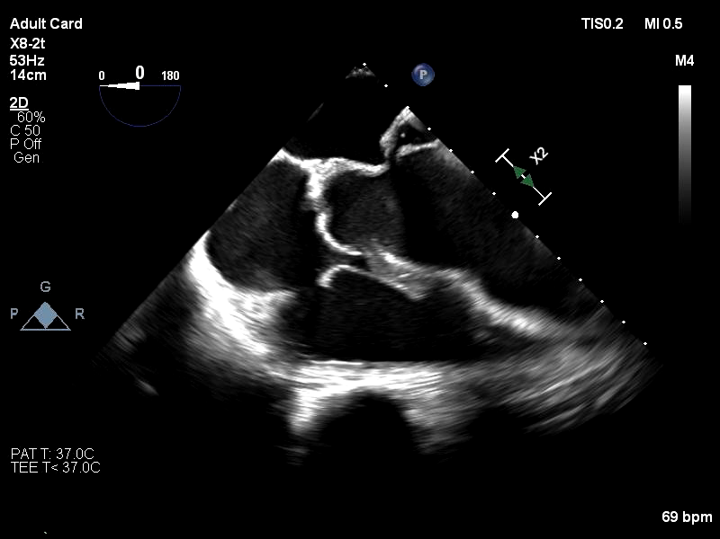

Relevant Test Results Prior to Catheterization

EKG showed normal sinus rhythm with ST segment elevation at V1-3 , inverted T wave at V4-6 , I ,aVL. Echocardiogram showed impaired LV systolic function, global wall hypokinesia, normal prosthetic aortic valve function with mild paravalvular leakage and bulging of aortomitral intervalvular fibrosa, suspected Aortomitral intervalvular fibrosa aneurysm. CT cardiac revealed pseudoaneurysm of the aortomitral intervalvular fibrosa with laminated thrombus with no LAA thrombus visualized.